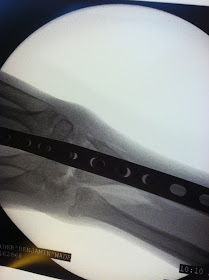

1. Praise God my Benjamin came through his surgery today. He has struggled with some pain due to spasms but has perked up this afternoon and is talking and even smiling a bit. The surgeon was able to fuse his wrist bones to correct the deformity and to lengthen tendons in his elbow for some range of motion there. We can not know how everything will turn out yet...but we do know -- and you can tell from my photo here -- that the arm is straight again! A big improvement from here:

And though I can not see through the cast...the x-rays look cool!